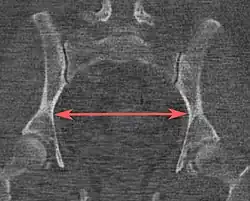

Pelvic inlet | Transverse diameter of the pelvic inlet | ![]() | ![]() Coronal plane | The iliopectineal lines, at widest transverse distance. | 13 to 14.5 cm.[4] |